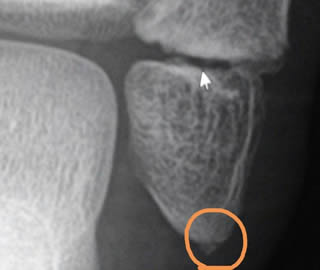

「左足じゃないんですね。ここの骨の欠片が離れてるのが気になります。」

てなわけで、病名「左腓骨遠位端骨折」